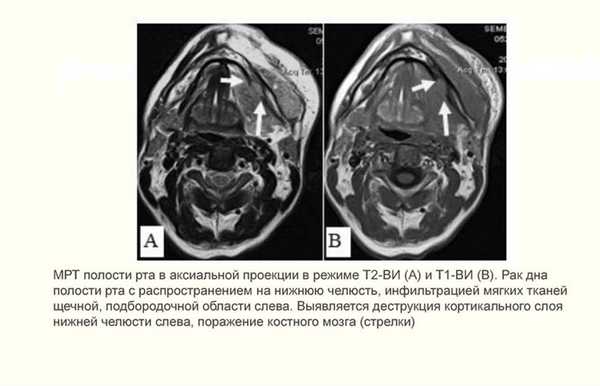

Рак дна полости рта

Данный вид опухоли составляет 10-15% всех раков полости рта. Дно ротовой полости образовано структурами между языком и подъязычной костью. Слизистая, выстилающая дно полости рта, имеет развитую подслизистую основу, состоящую из рыхлой соединительной ткани и клетчатки. Данная область богато кровоснабжается. Всё это создаёт благоприятные условия для роста опухоли, ее распространения и метастазирования.